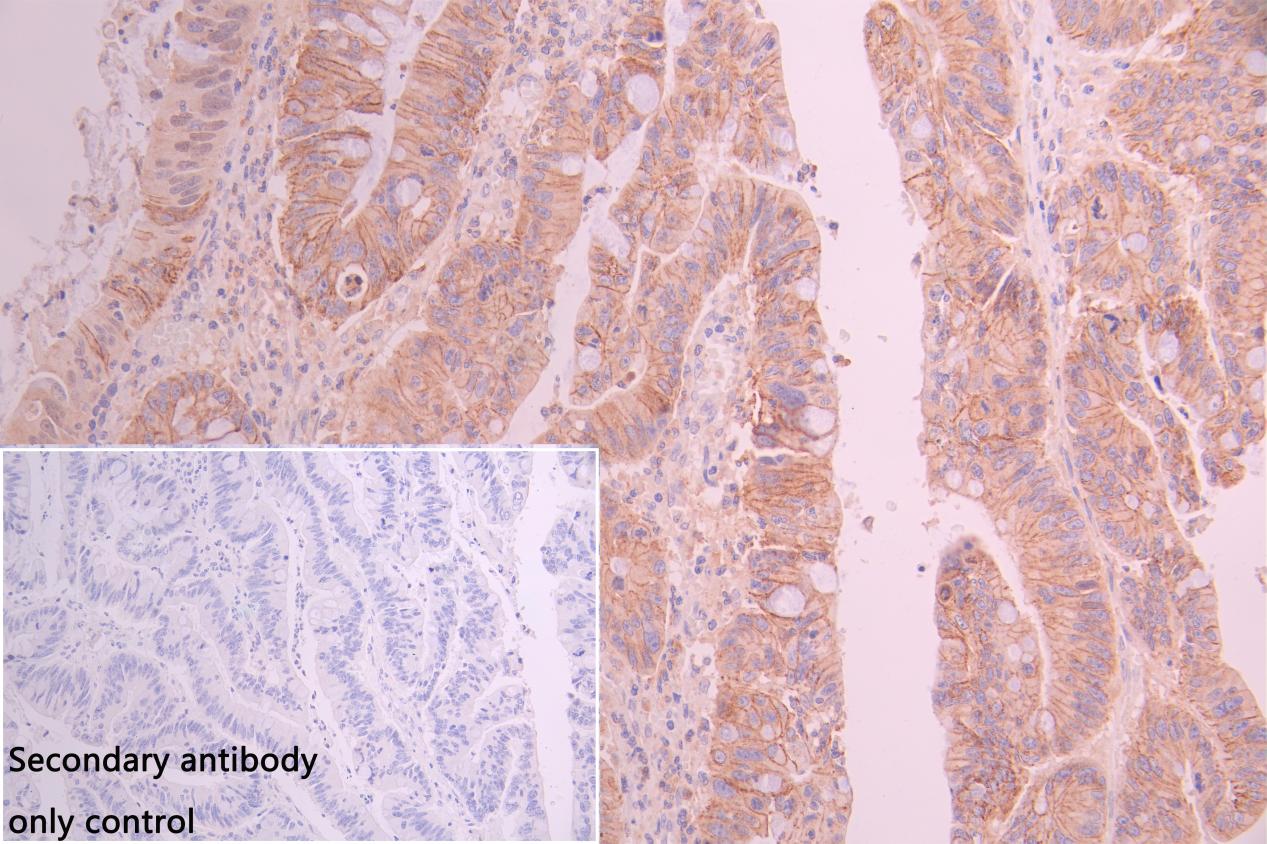

IHC image of CSB-PA015988LA01HU diluted at 1:100 and staining in paraffin-embedded human breast cancer performed on a Leica BondTM system. After dewaxing and hydration, antigen retrieval was mediated by high pressure in a citrate buffer (pH 6.0). Section was blocked with 10% normal goat serum 30min at RT. Then primary antibody (1% BSA) was incubated at 4°C overnight. The primary is detected by a Goat anti-rabbit polymer IgG labeled by HRP and visualized using 0.05% DAB. Secondary antibody only control: uses 1% BSA instead of primary antibody